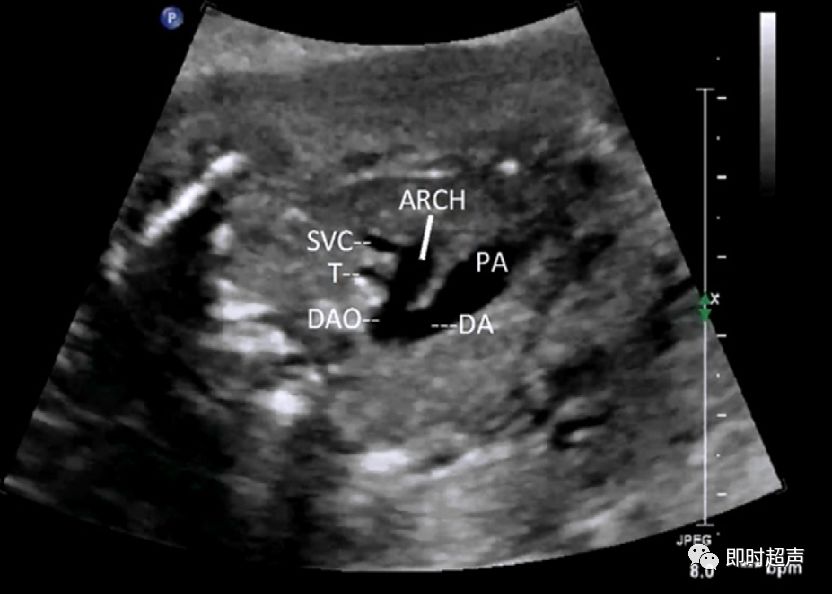

探到胎儿四腔心后,探头稍向胎儿头侧偏移即可显示三血管-气管切面,正常三血管-气管平面从左到右依次显示:肺动脉、主动脉弓、气管、上腔静脉。

- 从左到右依次是肺动脉、主动脉弓和上腔静脉

- 内径从左到右依次递减

- 主动脉弓位于气管的左侧

- 肺动脉和主动脉弓血流都流向脊柱,呈后向血流

- 肺动脉经动脉导管与主动脉弓共同汇入降主动脉